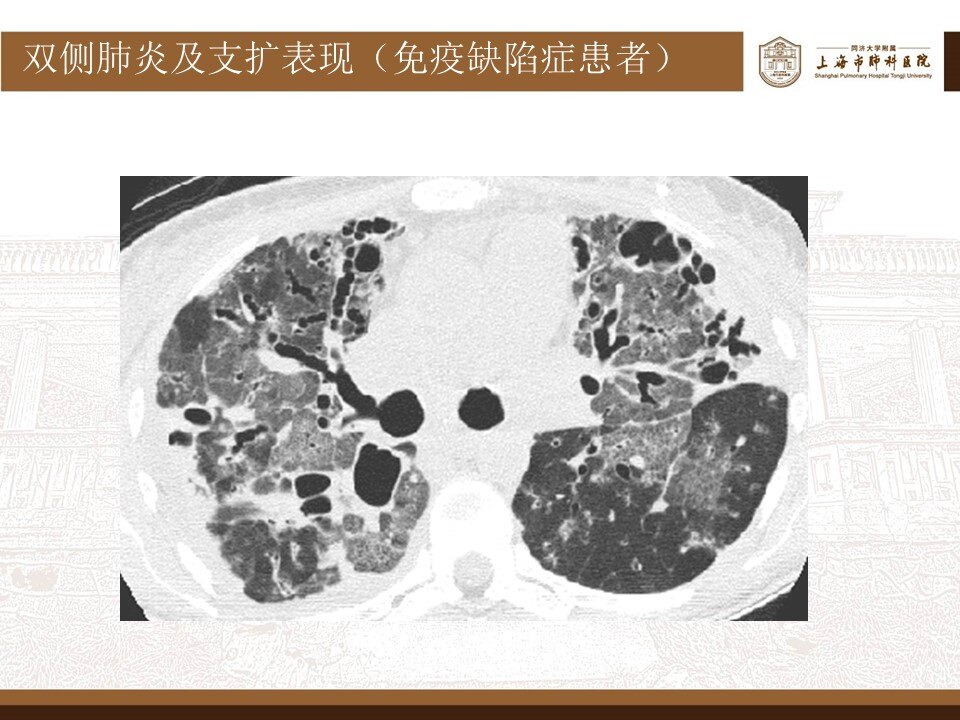

近期,随着新冠感染的普遍性,很多患者阳了之后, 非常紧张,非常焦虑,害怕有大白肺,就在当地医院拍了CT,结果大白肺,没有看到,意外地发现肺上有新发结节,或新发磨玻璃结节,再到网上一查,就更加焦虑了。

其实,这波omicron感染,确实肺炎比例比想象中要高,但很多都不会是大白肺,多数表现为双肺散发磨玻璃影,当然,也有单独的磨玻璃结节,特别容易表现为混合密度磨玻璃结节。其实很多新发的磨玻璃结节都是新冠肺炎,不用过于紧张,如果感染面积不大,一般临床上,也不需要特异性治疗,休息观察就行了。